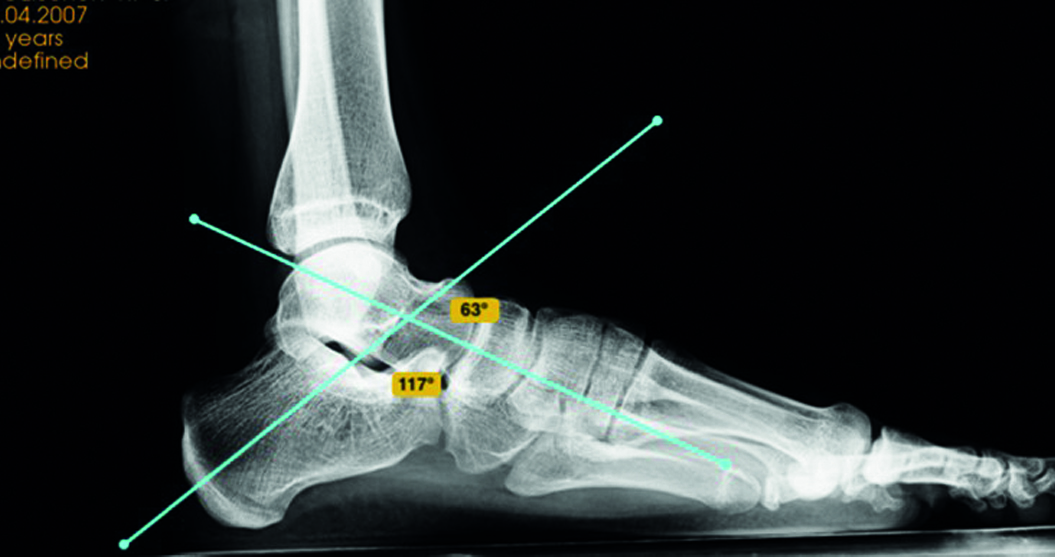

Рентгенография стоп под нагрузкой: оценивались такие показатели, как угол продольного свода стопы, который образуется пересечением двух касательных – одна к подошвенной поверхности пяточной кости, другая – к подошвенной поверхности первой плюсневой кости (в норме угол продольного свода стопы равен 125–130°, высота свода > 35 мм); угол Кайта, образованный пересечением продольных осей таранной и пяточной костей (норма 25–55 градусов); угол Meary – между первой плюсневой и таранной костью (в норме не должен превышать 4 градусов (рисунки 1, 2).

Рисунок 2. Рентгенограмма правой стопы в боковой проекции под нагрузкой. / Figure 2. X-ray of the right foot in the lateral projection under load.